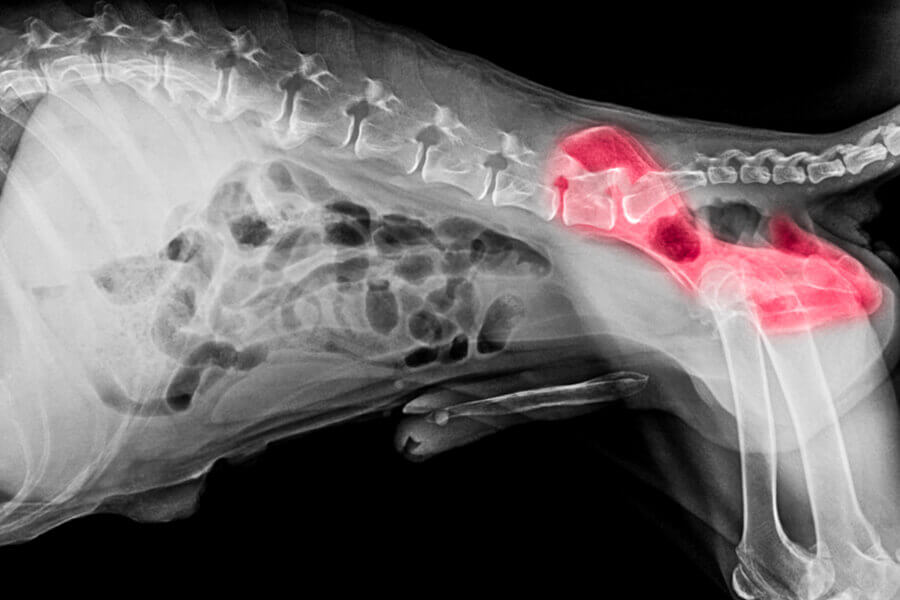

股関節形成不全は、関節部分の骨が変形していたり、股関節が緩んだりすることで起こる病気です。

生まれつき骨のゆがみや股関節の緩みがあると股関節がうまくかみ合わず、関節の中で炎症が起こります。